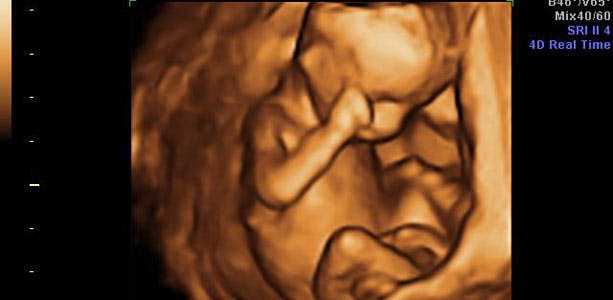

Gravid uge 15: Kønnet kan (måske) ses

Her kan din baby finde på at sutte på tommelfinger. Huden dækkes af de såkaldte lanugohår, som man mener virker til at holde fosterfedtet fast på barnets endnu tynde hud. Hvis barnet ligger i en god stilling, kan kønnet måske allerede nu ses ved ultralydsscanning. I slutningen af ugen måler barnet cirka 15 centimeter fra hoved til fod og vejer omkring 150 gram.